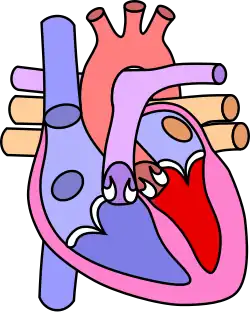

| Diagram of a healthy heart and one with tetralogy of Fallot | |

Tetralogy of Fallot (TOF), formerly known as Steno-Fallot tetralogy,[9] is a congenital heart defect characterized by four specific cardiac defects.[4] Classically, the four defects are:[4]

- Pulmonary stenosis, which is narrowing of the exit from the right ventricle;

- A ventricular septal defect, which is a hole allowing blood to flow between the two ventricles;

- Right ventricular hypertrophy, which is thickening of the right ventricular muscle; and

- an overriding aorta, which is where the aorta expands to allow blood from both ventricles to enter.

Four malformations

"Tetralogy" denotes four parts, here implying the syndrome's four anatomic defects.[2] This is not to be confused with the similarly named teratology, a field of medicine concerned with abnormal development and congenital malformations (including tetralogy of Fallot). Below are the four heart malformations that present together in tetralogy of Fallot:

| Pulmonary Infundibular Stenosis | A narrowing of the right ventricular outflow tract. It can occur at the pulmonary valve (valvular stenosis) or just below the pulmonary valve (infundibular stenosis).[4] Infundibular pulmonic stenosis is mostly caused by the overgrowth of the heart muscle wall (hypertrophy of the septoparietal trabeculae),[42] however, the events leading to the formation of the overriding aorta are also believed to be a cause. The pulmonic stenosis is the major cause of the malformations, with the other associated malformations acting as compensatory mechanisms to the pulmonic stenosis.[43] The degree of stenosis varies between individuals with TOF and is the primary determinant of symptoms and severity. This malformation is infrequently described as sub-pulmonary stenosis or subpulmonary obstruction.[44] |

| Overriding aorta | An aortic valve with biventricular connection, that is, it is situated above the ventricular septal defect and connected to both the right and the left ventricle. The degree to which the aorta is attached to the right ventricle is referred to as its degree of "override." The aortic root can be displaced toward the front (anteriorly) or directly above the septal defect, but it is always abnormally located to the right of the root of the pulmonary artery. The degree of override is extremely variable, with 5–95% of the valve being connected to the right ventricle.[42] |

| Ventricular septal defect (VSD) | A hole between the two bottom chambers (ventricles) of the heart. The defect is centered around the most superior aspect of the ventricular septum (the outlet septum), and in the majority of cases is single and large. In some cases, thickening of the septum (septal hypertrophy) can narrow the margins of the defect.[42] |

| Right ventricular hypertrophy | The right ventricle is more muscular than normal, causing a characteristic boot-shaped (coeur-en-sabot) appearance as seen by chest X-ray. Due to the misarrangement of the external ventricular septum, the right ventricular wall increases in size to deal with the increased obstruction to the right outflow tract. This feature is now generally agreed to be a secondary anomaly, as the level of hypertrophy tends to increase with age.[45] |